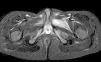

En la exploración de caderas presentaba dolor a la palpación en regiones inguinales y músculos aductores con limitación a la separación pasiva. No había limitación a las rotaciones de cadera y no se observaba hematoma, deformidad o tumefacción. En la analítica presentaba leucocitos 13.850/μl (N 11.770/μl, L 1.520/μl) con hemoglobina y recuento de plaquetas normales. La velocidad de sedimentación globular era de 50mm/h, la proteína C reactiva de 8mg/dl y la procalcitonina de 0,43ng/ml. La CPK era de 28U/l, siendo los parámetros de función hepática y renal normales. No se encontraron alteraciones en la radiografía de caderas. En la ecografía de caderas se apreciaba un discreto aumento del espesor de la cápsula anterior de ambas articulaciones con mínima cantidad de líquido intraarticular en el lado izquierdo (2,7mm de espesor). La resonancia magnética de caderas objetivó un engrosamiento y una alteración de la señal hiperintensa en secuencias T2 de la región de los aductores de forma bilateral con predominio izquierdo; en el músculo aductor largo izquierdo se apreciaba una imagen ovalada central, hipointensa en T1 e hiperintensa en T2, sugerente de colección (figs. 1 y 2). No se encontraron alteraciones en las articulaciones coxofemorales. Los hallazgos son compatibles con inflamación localizada en el músculo por piomiositis.